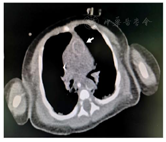

心超多次提示左心收缩功能减退,反复肺动脉高压(表1)。胸部CTA:升主动脉、胸主动脉、主动脉弓部及其分支血管壁广泛钙化;动脉导管部分未闭;冠状动脉未见异常(图1)。腹部CTA:腹主动脉及其分支(腹腔干、肠系膜上动脉、双肾动脉、双侧髂动脉及其分支)广泛血管壁钙化;腹主动脉管腔偏窄,腹主动脉分支纤细;肝、脾、胰腺、肾脏未见局灶性密度异常(图2)。基因检查(全外显子高通量测序,父母Sanger验证):ENPP1基因杂合突变,分别为来源母亲的NM_006208;exon7;c.783C>G(p.Y261X)。来源父亲的NM_006208;exon18;c.1786A>G(p.S590G),见图3。

临床症状在胎儿时期即可出现,异常钙化在胎龄18周时即有报道[3],胎儿时期可表现为羊水过多、胎儿窘迫、胎儿水肿。生后1周内起病的多数表现为心力衰竭、高血压、呼吸窘迫、发绀。后期起病的除上述表现外,也可表现为呕吐、拒奶、易激惹、生长迟缓[1]。随着年龄增长,也会出现血管外钙化,包括关节和内脏钙化。病理虽是确诊的金标准,但检查受限。实验室检查钙、磷、维生素D在正常水平[4]。有文献[5]对长期存活的患儿进行了随访,发现所有患儿在出生时血磷正常,随年纪增长平均在1岁半时出现低磷血症,2岁时出现佝偻病的比例为20%,而到13岁半时出现佝偻病的比例是100%。本案例中患儿查生化血磷在正常范围,四肢长骨片无骨质改变,与报道相符。影像学检查主要包括超声和CT。超声可帮助评估心功能,也可发现主动脉系统的广泛性管壁增厚、回声增强和管腔狭窄。CT可发现心脏瓣膜、肺动脉、主动脉及主动脉系统等大中动脉的钙化,部分病例还能发现关节周围软组织的钙化[6]。本案例为明确反复心功能衰竭和肺出血的原因进行了CTA检查,在平扫过程中即发现了广泛的主动脉系统钙化、部分管腔狭窄,提示CT平扫即可对本病有诊断作用,而增强扫描进一步排除了先天性心脏病及肺血管发育异常。基因检查多数可发现ENPP1基因异常,少数可发现ABCC6变异,其他基因变异有待进一步发掘。但需要注意的是这两个基因变异并不一定就表现为GACI,可有其他不同的疾病谱,如弹力纤维性假黄瘤、低磷血症佝偻病[7,8],故临床诊断中仍需结合病史及影像学、病理综合判断。